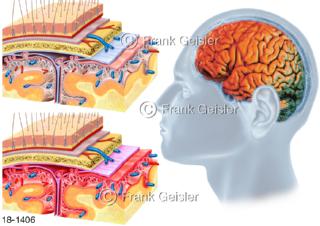

18-1406 Meningitis Hirnhautentzündung, Entzündung der Hirn- oder Rückenmarkshäute